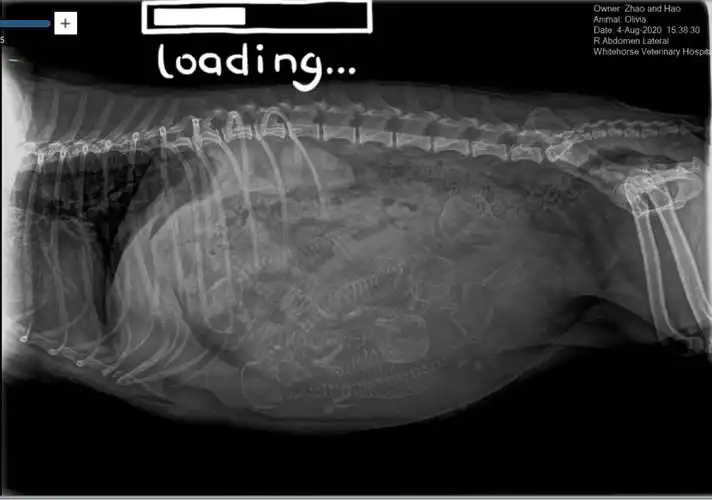

最近带ollie宝去拍了x光片之前看乳头有5个变大猜有五个宝宝为了确定